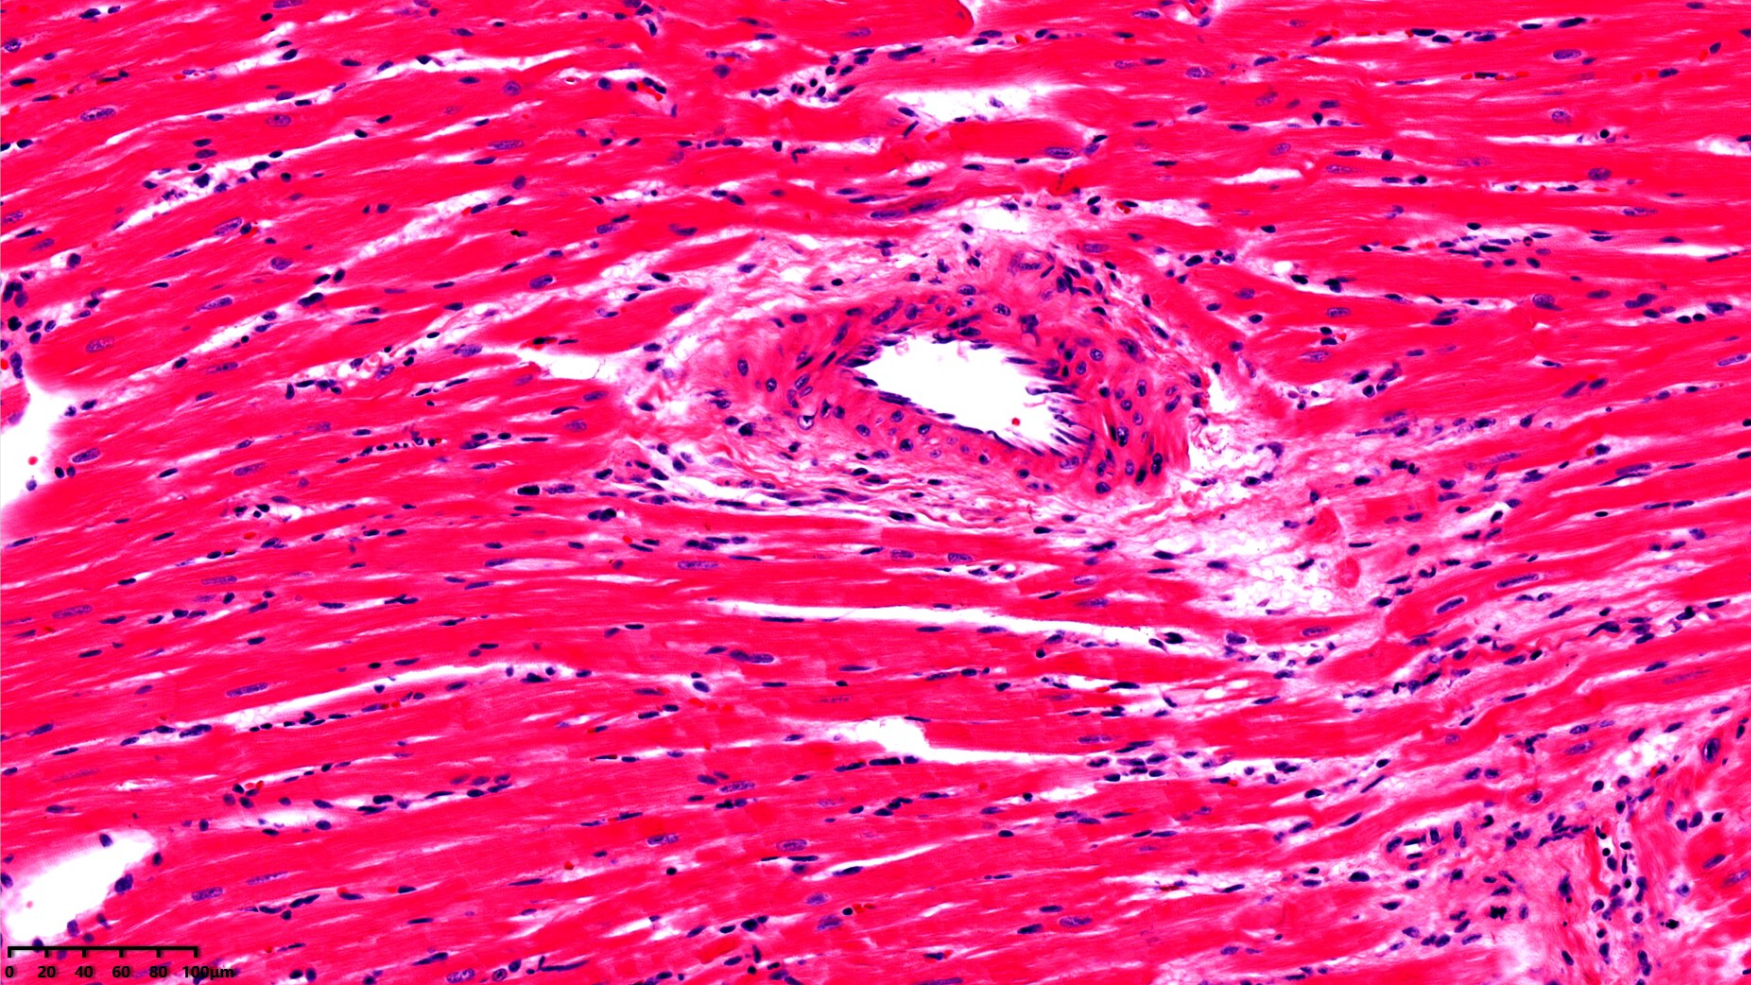

心脏组织病理

病理切片